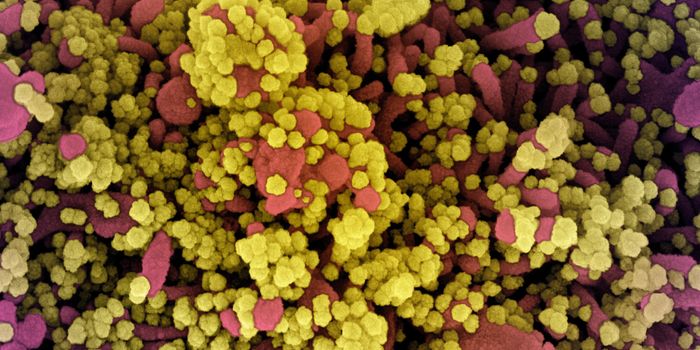

JUL 11, 2021MicrobiologyIn October 2020, what's now called the Delta variant of SARS-CoV-2 was first detected. It's now the most prevalent strai ...